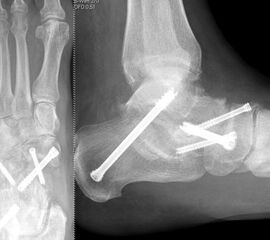

Es kommen verschiedene technische Möglichkeiten der operativen Versorgung in Frage.  Verwendung finden vor allem winkelstabile Plattensysteme, Schraubenosteosynthesen, Klammern, intraossäre Nagelsysteme, temporäre Kirschnerdraht-Transfixationen, Einbolzen von trikortikalem Span und Anlagerung von Spongiosa aus dem Beckenkamm oder dem Tibiakopf  (Abb. 2 und 3).

Die isolierte Arthrose der Bona Jäger Gelenkreihe (navikulocuneiforme Gelenk) ist selten und oft posttraumatisch. Meistens geht die navikulocuneiforme Arthrose mit einem schmerzhaften Pes planovalgus einher 2425. Letztlich werden die betroffenen Gelenkflächen angefrischt und mittels verschiedener Implantat-Möglichkeiten (s.o.) fusioniert. Bei gleichzeitiger Plattfußfehlstellung sollte diese ebenfalls adressiert werden 26 (Abb. 4). Ziel ist die Arthrodese in anatomischer Stellung der Gelenke.